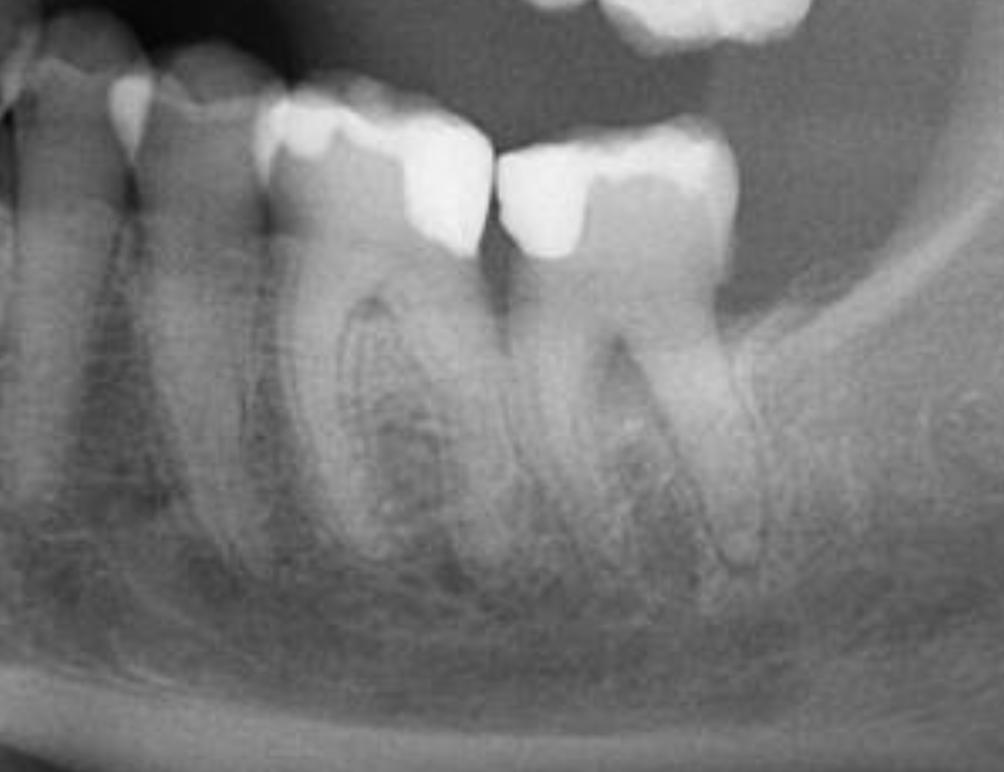

The patient was referred to our endodontic practice for evaluation and treatment of tooth 36. Clinically #36 had MOD composite restoration, a negative response to cold, and tenderness to percussion. Pre-op x-ray revealed #36 had a small periapical radiolucency associated with the Mesial root and a moderate size associated with the Distal root. Pulpal Necrosis with Symptomatic Apical Periodontitis. Endodontic diagnosis: Tooth #36 was accessed, located MB, ML, and DB and DL canals. Canals instrumented with EdgeFile X7 rotary files using a crown down technique. Pre-Op – James A. Wealleans, D.M.D, American Board Certified Endodontist, Adj Professor, Clinician Sydney, Australia